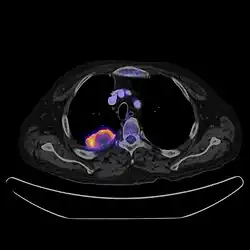

PET CT

PET-CT scan of chest

Positron emission tomography–computed tomography is a hybrid CT modality which combines, in a single gantry, a positron emission tomography (PET) scanner and an X-ray computed tomography (CT) scanner, to acquire sequential images from both devices in the same session, which are combined into a single superposed (co-registered) image. Thus, functional imaging obtained by PET, which depicts the spatial distribution of metabolic or biochemical activity in the body can be more precisely aligned or correlated with anatomic imaging obtained by CT scanning.[24]

PET-CT gives both anatomical and functional details of an organ under examination and is helpful in detecting different type of cancers.[25][26]